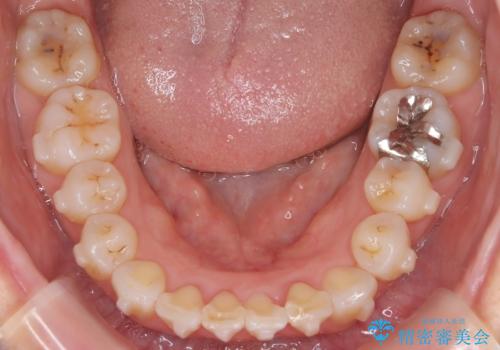

- 「歯のガタつきが気になる」「前歯の真ん中がずれている」との主訴で来院されました。診察の結果、上下の歯列に中等度の叢生(凸凹)があり、特に前歯の位置のずれ(正中の偏位)が目立つ状態でした。見た目だけでなく、かみ合わせにも影響を与える可能性があるため、全体的なバランスの改善が必要と診断しました。

目立たない装置をご希望されたため、取り外しができる透明なマウスピース型矯正装置「インビザライン」を用いた治療を選択。歯列全体をデジタルでシミュレーションし、叢生の改善と正中の位置を一致させることを目標とした治療計画を立てました。

治療はインビザラインを使用し、1~2週間ごとに新しいマウスピースに交換しながら段階的に歯を移動させていきました。特に上下の正中が揃うよう、奥歯や前歯の位置関係に注意を払いながら細かく設計を調整。途中の確認でも、左右のバランスが取れてきたことをご本人も実感されていました。

治療期間は約1年半で、ガタついていた歯列はきれいに整い、上下の前歯の真ん中もぴったりと揃えることができました。透明なマウスピースのため周囲に気づかれず治療が進み、快適に続けられたとの感想もいただいています。